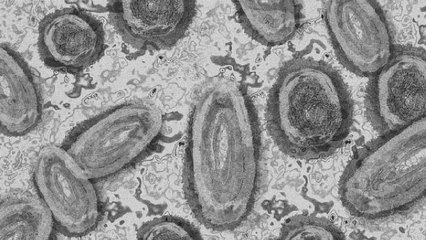

Viruela del mono: los retos para Colombia y el mundo